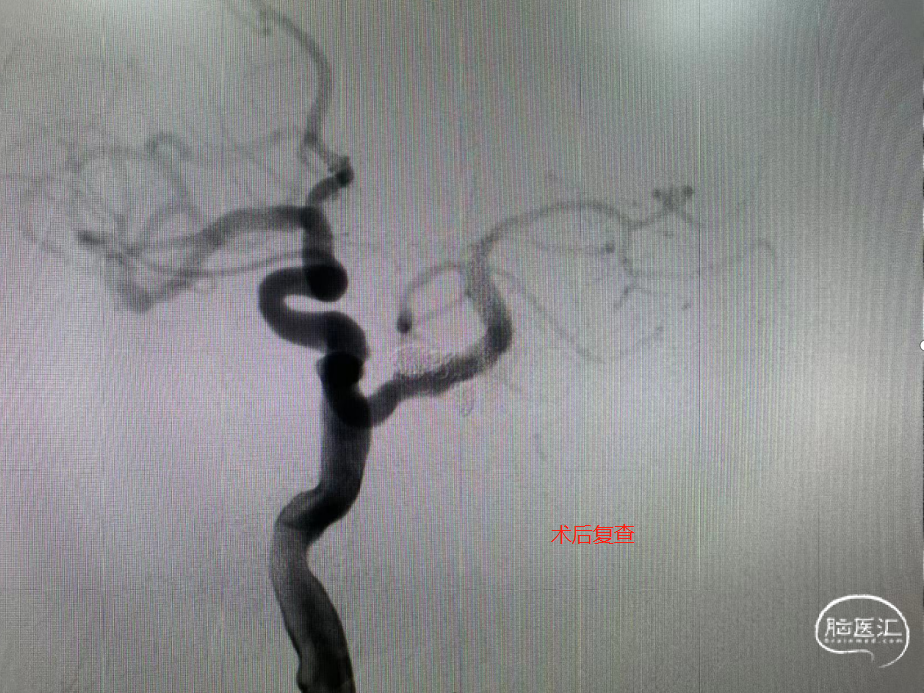

【病例夹】王飞教授:原始三叉动脉瘤栓塞

手术过程

术者体会